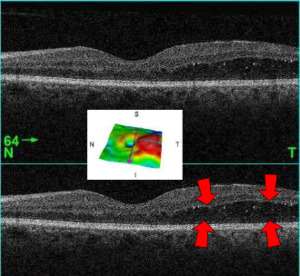

MacularEdema OCT 2-3D LeftE with-out arrows.png

A 61-year-old man with medical history of type 2 diabetes that presents a macular edema, evidenced by an OCT (the edema marked with arrows). The central image is a 3D reconstruction of the retinal thickness (the edema is coloured in red).